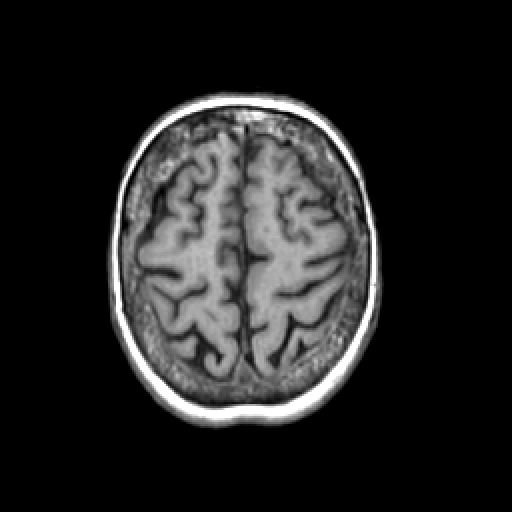

T1-weighted structural MR: Slice 42

Slice 42